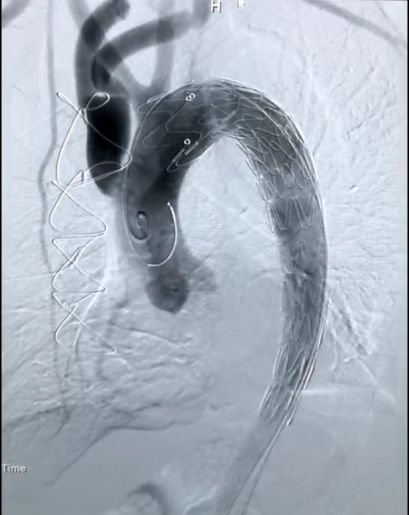

但是,“杂交手术”对医护团队配合度的要求非常高,需要外科手术与内科介入的无缝连接。首先,由心脏外科谢少波主任、王凯教授团队先为王先生实施了全麻下“右锁骨下动脉转流+左锁骨下动脉转流”,利用一根“Y”型人工血管将左、右锁骨下动脉与升主动脉相连接,完成双侧锁骨下动脉重建,确保患者双侧上肢的血供。

在此基础上,黄铮教授带领王慧勇博士等心血管内科介入团队进行了微创“主动脉腔内隔绝术”,成功植入主动脉覆膜支架,封堵主动脉夹层破口。术后,王先生被送入心血管内科监护室,在医护人员的严密监护和精心治疗下,恢复良好,双侧上肢活动正常,血液供应完全没有受到影响,2月27日已经转入普通病房。